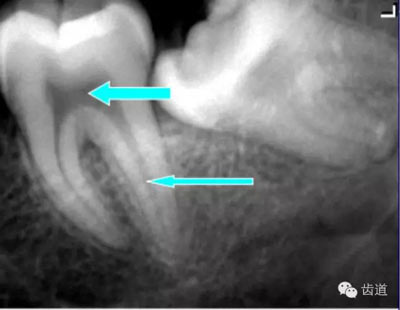

由升支前緣下部斜向前下方,為一密度高的帶狀影像。常重疊在第二、三磨牙牙冠處、頸部或根部,使牙髓室或根管不能清晰顯示

5)下頜管:

位于磨牙牙根尖下方,呈寬約為0.4cm凹面向下邊緣整齊的帶狀密度低的影像,其兩側(cè)有密度高的線條狀影像,為下頜管骨密質(zhì)